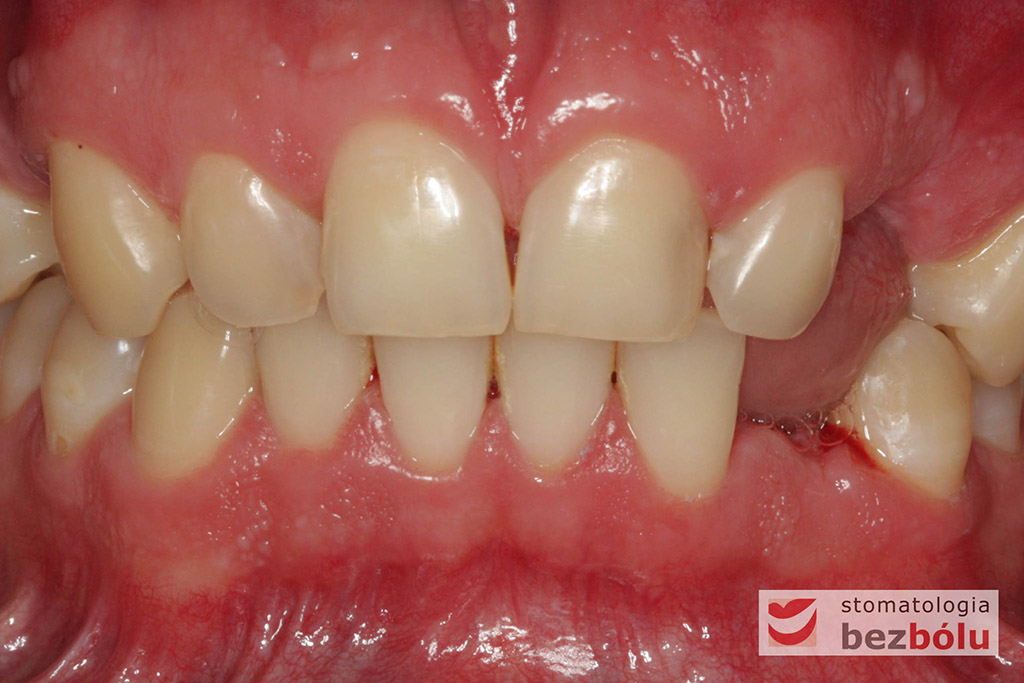

Młody pacjent w wieku lat 28 po wstępnym rozpoznaniu, ze zdiagnozowanym złamaniem kła zarówno górnego jak i dolnego, został skierowany na terapię implantoprotetyczną, prowadzoną przez lekarza dentystę Marcina. W świetle braku możliwości wykonania ekstruzji ortodontycznej i zachowawczego podejścia do leczenia, podjęto decyzję o usunięciu obu zębów, zastosowaniu ułatwiającej gojenie procedury A-PRF i przygotowaniu pacjenta do zabiegu implantologicznego, dodatkowo uzupełnionego o wprowadzenia implantu w miejscu braku zębowego w pEdytujozycji pierwszego przedtrzonowca w szczęce po stronie prawej.